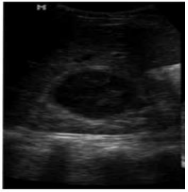

Uma mulher de 17 anos, gestação de 20 semanas, com febre (37,8ºC) foi encaminhada para realização de exame de ultrassonografia renal. O EAS mostrava piúria (20 a 30/campo). A paciente já se encontrava em tratamento com cefalexina, 500 mg VO, três vezes ao dia, que foi mantido por 14 dias. Segue USG realizada:

Corte longitudinal ecográfico do rim direito, mostrando

uma lesão hipecoica bem definida, medindo 48,0mm

Fonte: Vol. 10 • 14ª Edição • março DE 2011 | rbus 21

Qual diagnóstico para paciente atendida: